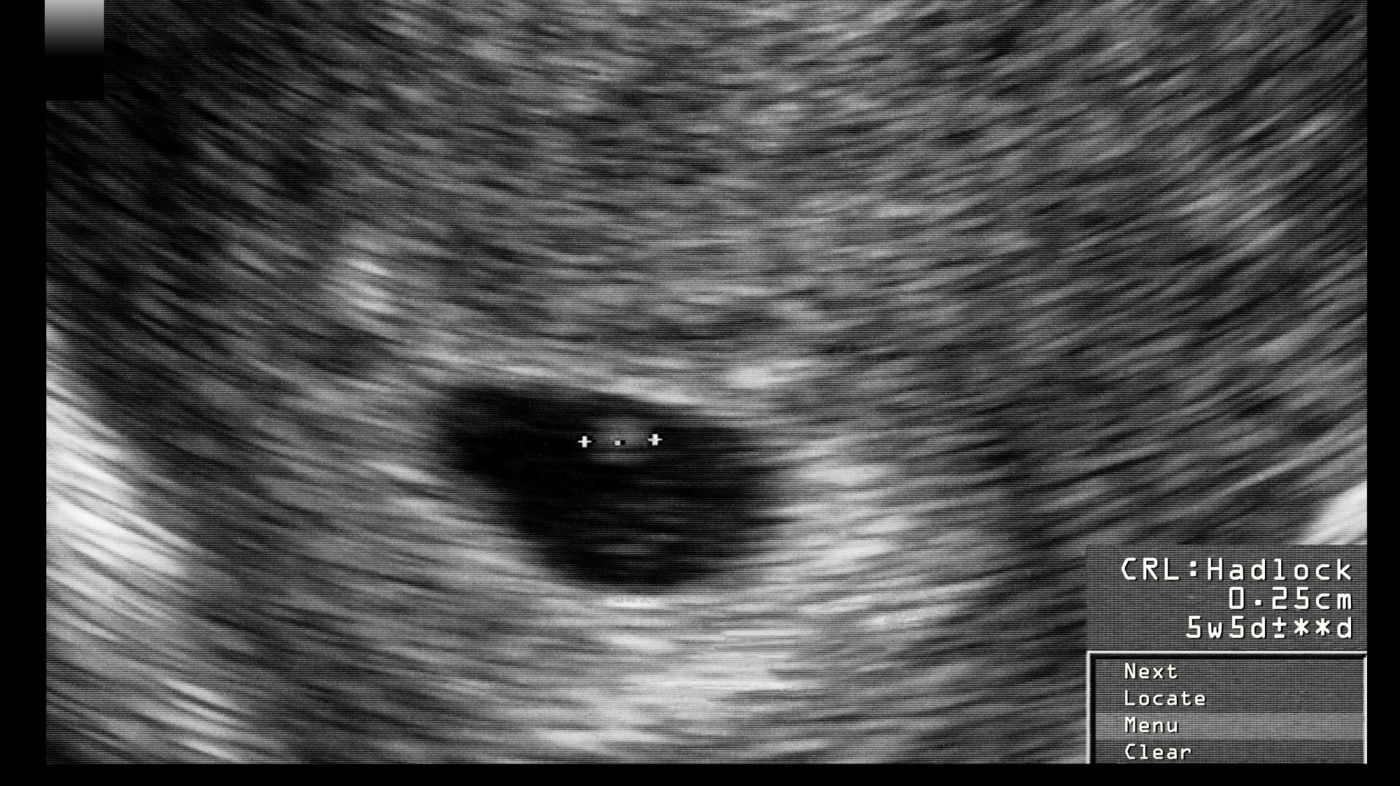

In der Regel kann man die Fruchthöhle etwa ab der 5. Schwangerschaftswoche im Ultraschall erkennen. Das ist ungefähr eine Woche nach dem Ausbleiben der Periode. Aber das ist nur ein Richtwert! Manchmal dauert es etwas länger. Und manchmal geht es schneller. Jeder Körper tickt anders.

Denk dran: Die Schwangerschaftswoche wird ab dem ersten Tag der letzten Periode berechnet. Das bedeutet, dass du in der 5. Woche vielleicht erst seit drei Wochen schwanger bist (wenn man vom Zeitpunkt der Befruchtung ausgeht). Verwirrend? Ja, ein bisschen! Aber keine Sorge, dein Arzt oder deine Ärztin wird dir alles genau erklären.

Wenn die Fruchthöhle gefunden ist, geht es erst richtig los! Dann wird nach dem Dottersack gesucht, der die erste Nahrung für den Embryo liefert. Und bald darauf, meist so um die 6. Schwangerschaftswoche, kann man dann auch das kleine Herzchen schlagen sehen! Das ist ein unvergesslicher Moment, der einen einfach sprachlos macht.